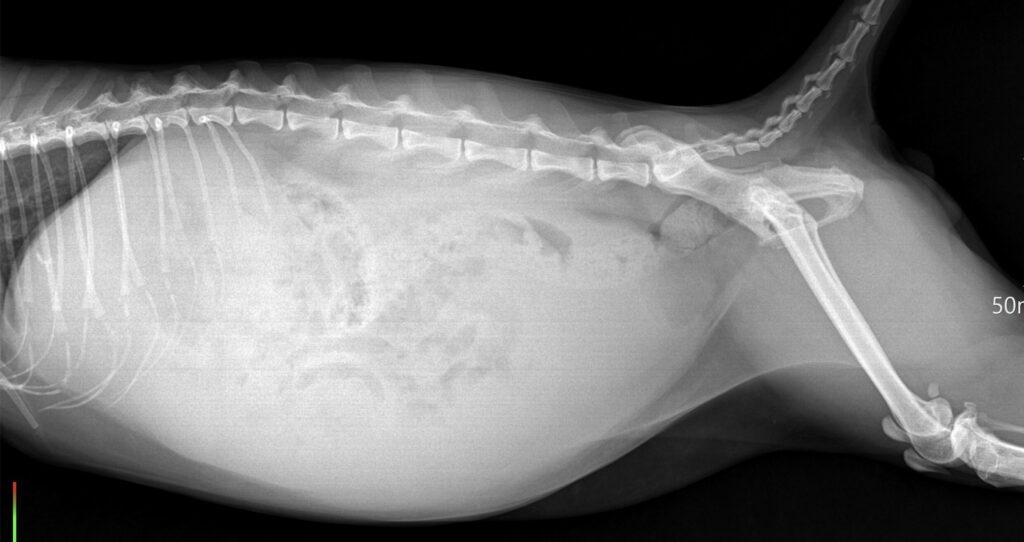

確認のため、レントゲンとエコー検査。しっかりと腹水。